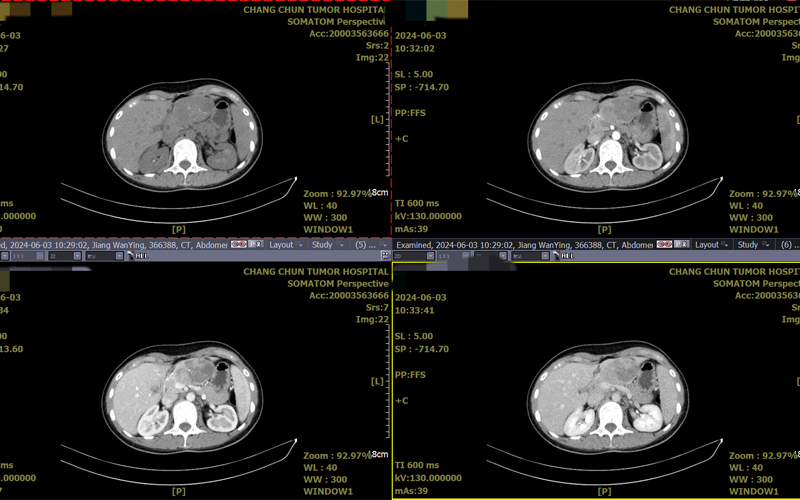

今年6月份,小姜收到了梦寐以求的硕士研究生通知书,然而,此时她的肚子疼痛越发频繁,腹胀更加严重。家人发现小姜身体不对劲,坚持让她去医院检查。当小姜来到医院检查时,医生的诊断结果让她大吃一惊,原来她的胰体尾部有占位性病变,胰腺肿瘤的可能性很大!这样的结果让小姜和她的家人一时之间都无法接受...

收治入院完善了相关检查后,王凯民指出该病灶为实性假乳头状瘤的可能性较大,这种肿瘤是发生于胰腺的一种比较罕见的外分泌肿瘤,在临床上发病率很低,需尽快手术治疗。

完善术前检查后,由王凯民主任主刀,在胃肠肝胆胰外科和麻醉科的配合下,为小姜精准实施“保留脾脏的胰体尾切除术”。术中发现小姜的胰尾部病灶约7厘米,与脾脏关系密切,在保留脾动静脉的基础上,将肿瘤及部分胰体尾切除。术中很好的控制了出血,并未出现术中输血的情况,胰体尾切除之后脾脏无明显血运改变,手术非常成功。